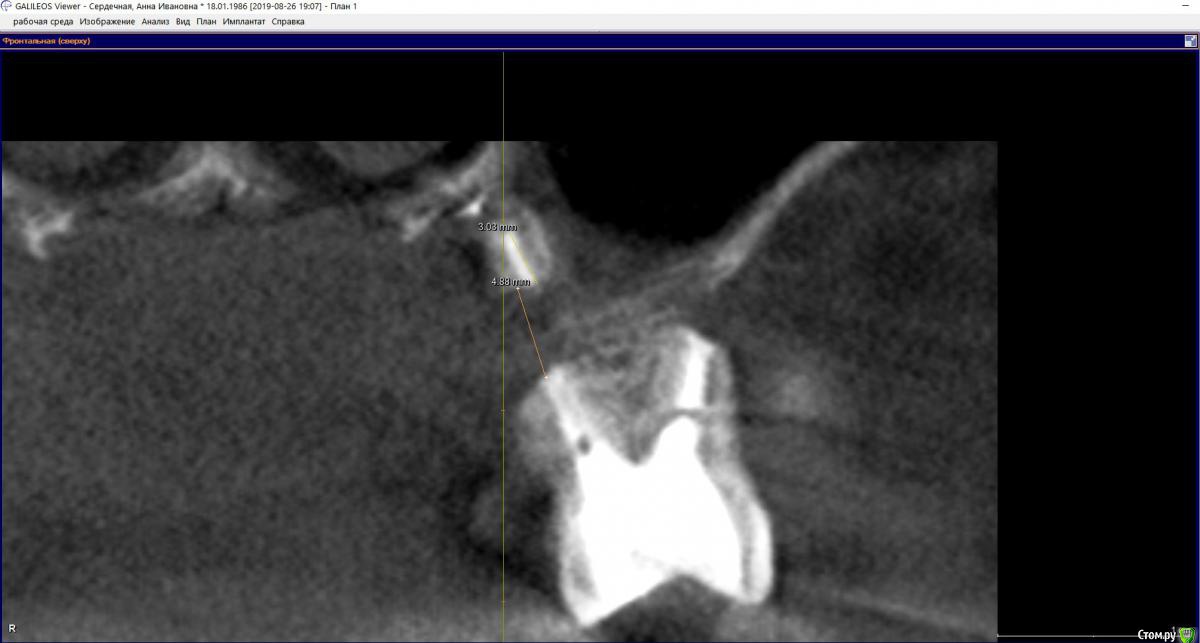

hichin Опубликовано 27 августа, 2019 Поделиться Опубликовано 27 августа, 2019 Здравствуйте, уважаемые стоматологи! Проблемный многострадальный зуб-моляр (26): Дважды попытки удаления кисты левой г/п, вторая попытка удачная, а также гайморотомия и септопластика.Неудачное эндодонтическое лечение, далее повторная попытка перелечивания (смена паст, симптоматика не уходила), которая закончилась сменой стоматолога и лечением с микроскопом. После пломбировки каналов снизилась симптоматика, но пазуха все равно реагировала небольшим утолщением слизистой + любая простуда давала сильную боль на пазуху + зуб. Врачи клиники советовали сделать резекцию. Лоры говорили, что проблема не с их стороны. В члх сделали резекцию с обратной пломбировкой.P.s. так долго эпопея с зубом длится, т.к. все специалисты в один голос говорили о том, что удаление зуба и последующая установка имплантата не факт, что избавит от проблем и будет вообще возможна.Симптоматика c резекцией не ушла.Срезы из свежего КТ прикрепляю. Если можно, прокомментируйте, пожалуйста, срезы. Ссылка на комментарий

hichin Опубликовано 28 августа, 2019 Автор Поделиться Опубликовано 28 августа, 2019 Здравствуйте! По этим срезам изменения а пазухе не значительные,в пределах нормы,характерные для хронического процесса,наличие или отсутствие моляра на него никак не скажется,это самостоятельное заболевание. Над моляром достаточно по..работали,в перспективе он удаляется и замещается на имплант Благодарю вас за ответ.А как быть с оставшимся фрагментом небного корня (если я правильно понимаю, врач удалил не верхушку корня, а как бы середину корня). Реально ли его извлечь и как (через лунку удаленного зуба, через пазуху, тем же путем, что не дошел врач члх)? Основная симптоматика как раз с небной стороны у меня. Ссылка на комментарий